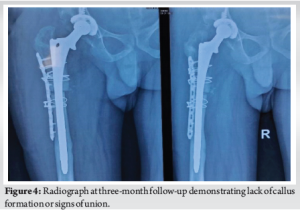

With the patient in left lateral decubitus position, the hip joint was exposed through a direct lateral approach extended distally (Hardinge technique). The incision was started at 5 cm proximal to the greater trochanter and extended distally to 10 cm below the greater tuberosity. Serial acetabular reaming was done, followed by cementless acetabular cup placement and fixation using two acetabular screws. Serial femoral broaching was done, and a long stem was used for the femur. Reduction was difficult due to the proximal migration of the greater trochanter. Hence, to aid the reduction, a subtrochanteric osteotomy was performed. The femur was exposed laterally, and subtrochanteric osteotomy was done using an osteotome and oscillating saw at the site of maximum deformity. Osteotomy site was fixed using a ten-hole locking compression plate laterally, fixed proximally and distally to the osteotomy site using 18G Stainless Steel wire, and a long stem femoral implant (solution stem) was used. Intramedullary fit was assessed using fluoroscopy. Range of movement and stability of the implant were assessed before closure. Post-operative radiograph showed signs of a well-positioned implant (Fig. 3). Post-operatively, range of movement and strengthening exercises were started the next day. The patient was started on painkillers. Low molecular weight heparin was administered for 7 days, and Apixaban 2.5 mg twice daily was continued for 3 months to prevent deep vein thrombosis. The patient was mobilized after three months of surgery. However, it was ensured that the range of movement and strengthening exercises were carried out. Initially, the patient was advised to perform hip abductor and core strengthening exercises. The patient was first followed up at 14 days of surgery for stitch removal, and then followed up at each month. Serial radiographs were done, and the wound condition, movement, and functions of the joint were assessed at each follow-up. At 3 months of follow-up, the patient still complained of pain in the right thigh and difficulty in movement. Furthermore, there were no radiological signs of healing (Fig. 4 for Radiograph). Hence patient was administered injections of orthobiologics to improve healing. The patient was given a BMAC injection at three months after the surgery, as the osteotomy was suspected to progress to non-union. The patient also received three doses of PRP injection at 4 months after surgery, 8 months post-operatively, and 10 months after surgery. All injections were given in a minor theatre, under all aseptic precautions with autologous preparation of BMAC and PRP. BMAC was prepared after aspiration of bone marrow and after centrifugation in the centrifuge machine. BMAC was injected into the fracture site. PRP was prepared after the collection of 30 mL of blood from the antecubital vein. Centrifugation was done, and the PRP prepared was activated with the activator, and the PRP was injected into the fracture site. The patient was then followed up at 1 year from the date of surgery. The patient has significantly improved results and was able to carry out daily activities. Radiograph also showed significant improvement in terms of callus formation (Fig. 5).